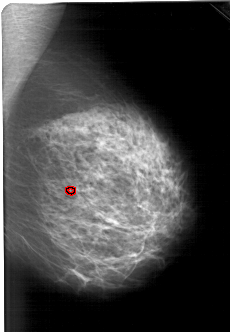

A_1374_1.RIGHT_CC

RIGHT_CC LINES 6091 PIXELS_PER_LINE 3616 BITS_PER_PIXEL 12 RESOLUTION 43.5 OVERLAY

FILE: A_1374_1.RIGHT_CC.OVERLAY

TOTAL_ABNORMALITIES 1

ABNORMALITY 1

LESION_TYPE CALCIFICATION TYPE PLEOMORPHIC DISTRIBUTION CLUSTERED

ASSESSMENT 4

SUBTLETY 2

PATHOLOGY BENIGN

TOTAL_OUTLINES 1

BOUNDARY